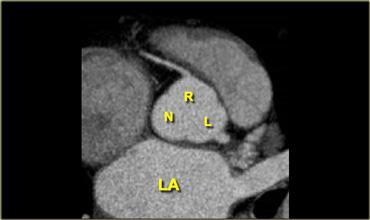

Van động mạch chủ có ba lá van, mỗi lá có cấu hình dạng lá van hay hình chén.

Chúng được gọi là lá van vành trái (L), lá van vành phải (R) và lá van không vành sau (N).

Ngay phía trên các van động mạch chủ có các chỗ giãn giải phẫu của động mạch chủ lên, còn được gọi là xoang Valsalva.

Xoang động mạch chủ trái là nơi xuất phát của động mạch vành trái.

Xoang động mạch chủ phải nằm ở phía trước, là nơi xuất phát của động mạch vành phải.

Xoang không vành nằm ở phía bên phải.